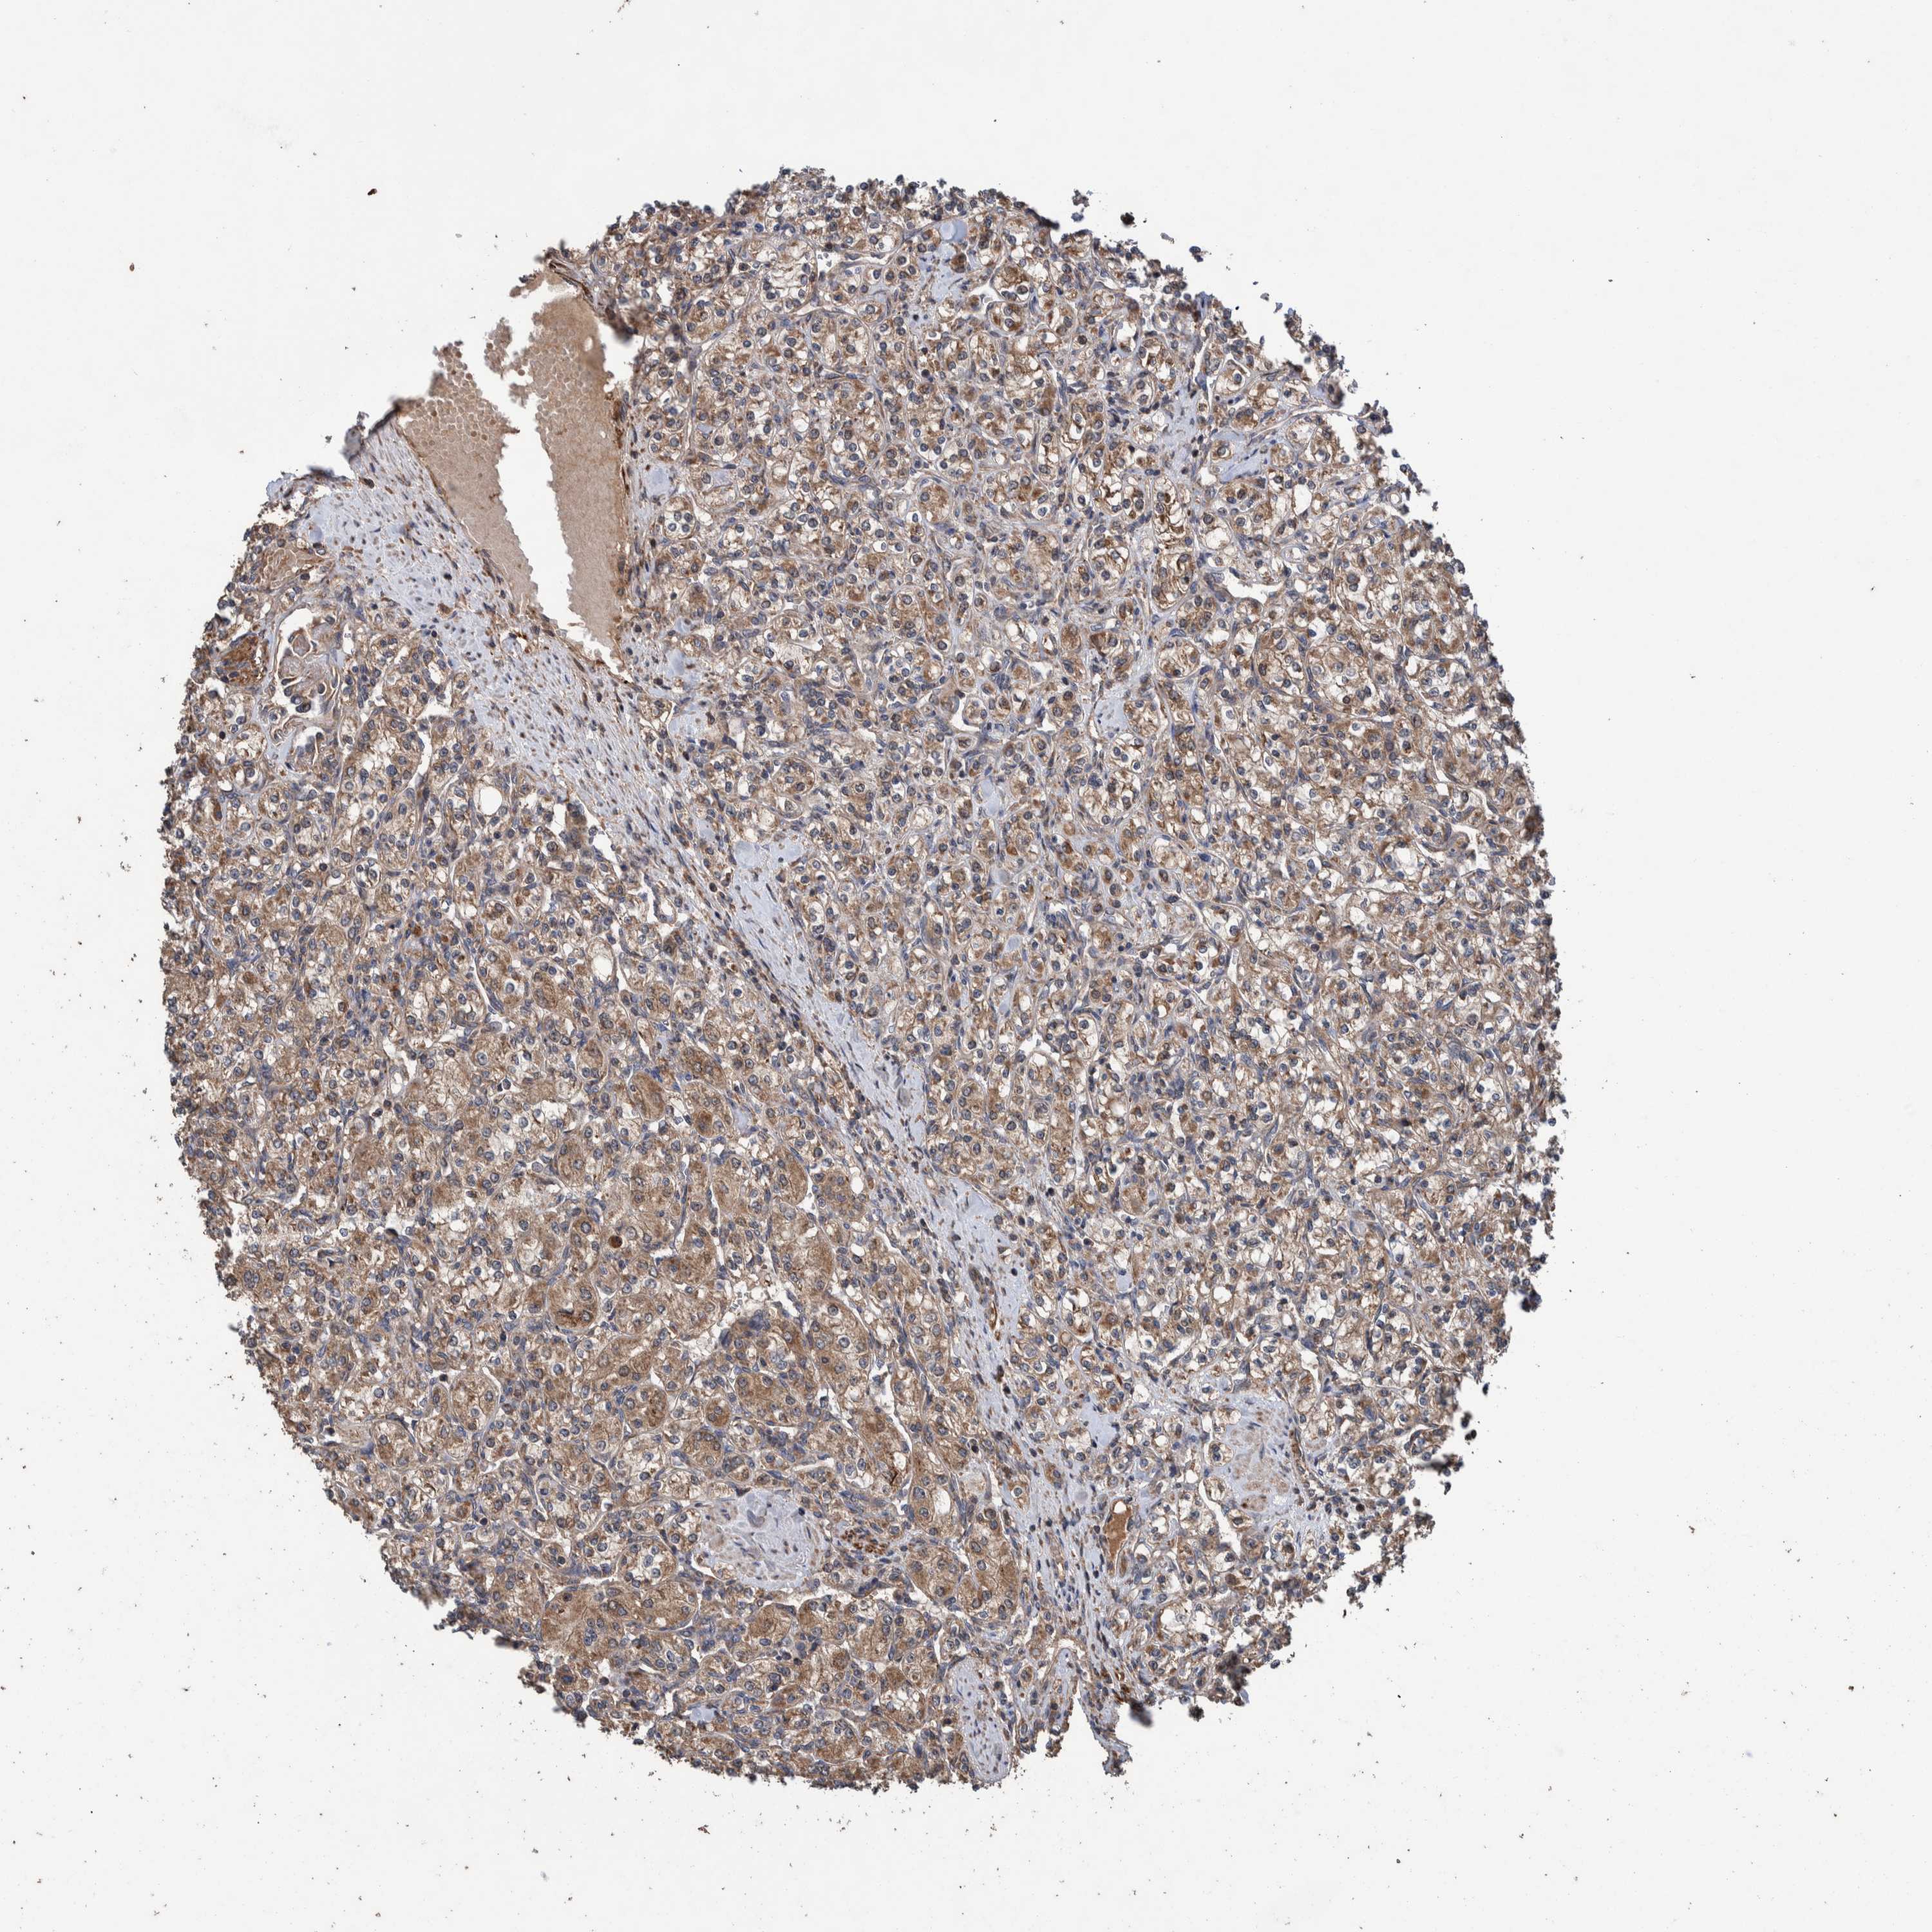

KIDNEY RENAL CLEAR CELL CARCINOMA (VALIDATION) - Interactive survival scatter ploti

The Survival Scatter plot shows the clinical status (i.e. dead or alive) for all individuals in the patient cohort, based on the same data that underlies the corresponding Kaplan-Meier plots. Patients that are alive at last time for follow-up are shown in blue and patients who have died during the study are shown in red.

The x-axis shows the expression levels (FPKM) of the investigated gene in the tumor tissue at the time of diagnosis. The y-axis shows the follow-up time after diagnosis (years). Both axes are complimented with kernel density curves demonstrating the data density over the axes. The top density plot shows the expression levels (FPKM) distribution among dead (red) and alive patients (blue). The right density plot shows the data density of the survived years of dead patients with high and low expression levels respectively, stratified using the cutoff indicated by the vertical dashed line through the Survival Scatter plot. This cutoff is automatically defined based on the FPKM cutoff that minimizes the p-score. The cutoff can be changed by dragging the vertical line or by entering a cutoff value in the square labeled "Current cut-off".

Under the Survival Scatter plot the p-score landscape (black curve; left axis) is shown together with dead median separation (red curve; right axis). Dead median separation is the difference in median mRNA expression between patients who have died with high and low expression, respectively. It is calculated as follows: median FPKM expression of dead patients with high expression - median FPKM expression of dead patients with low expression. This is intended to aid the user in visually exploring custom cutoffs and the associated p-scores and dead median separation.

Individual patient data is displayed and can be filtered by clicking on one or more of the category buttons on the top of the page. Categories describing expression level and patient information include: high, low, alive, dead, female, male and tumor stages. The scale of the x-axis can be toggled between linear and log-scale by clicking on the "x log" button. Mouse-over function shows TCGA ID, patient information and mRNA expression (FPKM) for each patient.

& Survival analysisi

Kaplan-Meier plots summarize results from analysis of correlation between mRNA expression level and patient survival. Patients were divided based on level of expression into one of the two groups "low" (under cut off) or "high" (over cut off). X-axis shows time for survival (years) and y-axis shows the probability of survival, where 1.0 corresponds to 100 percent.

TRIM16 is potential prognostic, high expression is unfavorable in Kidney Renal Clear Cell Carcinoma (validation)

Best expression cut offi

Based on the FPKM value of each gene, patients were classified into two groups and association between prognosis (survival) and gene expression (FPKM) was examined. The best expression cut-off refers the FPKM value that yields maximal difference with regard to survival between the two groups at the lowest log-rank P-value. Best expression cut-off was selected based on survival analysis .

When clicking on this number, the vertical dashed line indicating cut-off, the interactive survival plot, and the Kaplan-Meier curve will be adjusted to show results based on the best expression cut-off.

: 13.11

TCGA RNA samplesi

RNA-seq data is reported as average FPKM (number Fragments Per Kilobase of exon per Million reads), generated by the The Cancer Genome Atlas (TCGA) .

Normal distribution across the dataset is visualized with box plots, shown as median and 25th and 75th percentiles. Points are displayed as outliers if they are above or below 1.5 times the interquartile range. FPKM values of the individual samples are presented next to the box plot.

Average pTPM 11.6

Number of samples 100